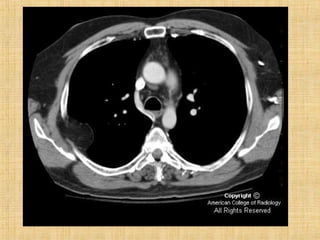

As principais informações do documento são: 1. Discute os padrões de doença pulmonar causados por metástases, incluindo nódulos, espessamento intersticial e obstrução das vias aéreas. 2. A prevalência de metástases pulmonares varia de 30-55% dependendo do tumor primário, e são mais comuns em pacientes acima de 50 anos. 3. Os achados clínicos mais comuns são dispneia, hemoptise e febre, enquanto exames de escarro ou lavado brô